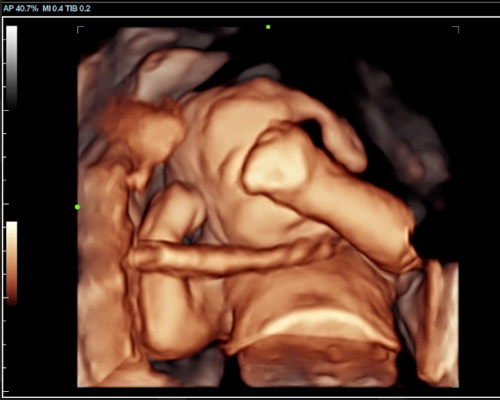

A 3D/4D bonding scan combined with a heartbeat bear near Wakefield offers a unique way to experience both visual and emotional connection before birth.

A 3D scan captures detailed still images of your baby’s face and body, while a 4D baby scan Wakefield allows you to see those images in motion. You may notice movements such as stretching, turning, or subtle expressions, making the experience feel more real.

With a 4D baby ultrasound Wakefield, this technology allows you to see your baby with greater clarity and depth. The result is softer, more lifelike visuals that can feel closer to a photograph than a traditional scan.

Our Scans